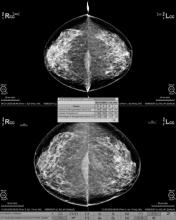

Intelerad Medical Systems introduces new tomosynthesis support for InteleViewer, enabling expanded breast imaging interpretation for the IntelePACS or InteleOne reading and reporting platforms. Using InteleViewer’s flexible hanging protocol layouts, radiologists can quickly step through cases for mammography screening or diagnosis, using tomosynthesis 3-D images to advance women’s health.

“Tomosynthesis really allows us to look through the breast, slice by slice, in a way that we haven’t been able to before,” explains Beth Whiteside, M.D., breast imaging specialist at Albany Medical Center and radiologist with Community Care Physicians. “It takes away that vexing issue of tissue overlap and allows us to look underneath. I think it is every radiologist’s dream.”